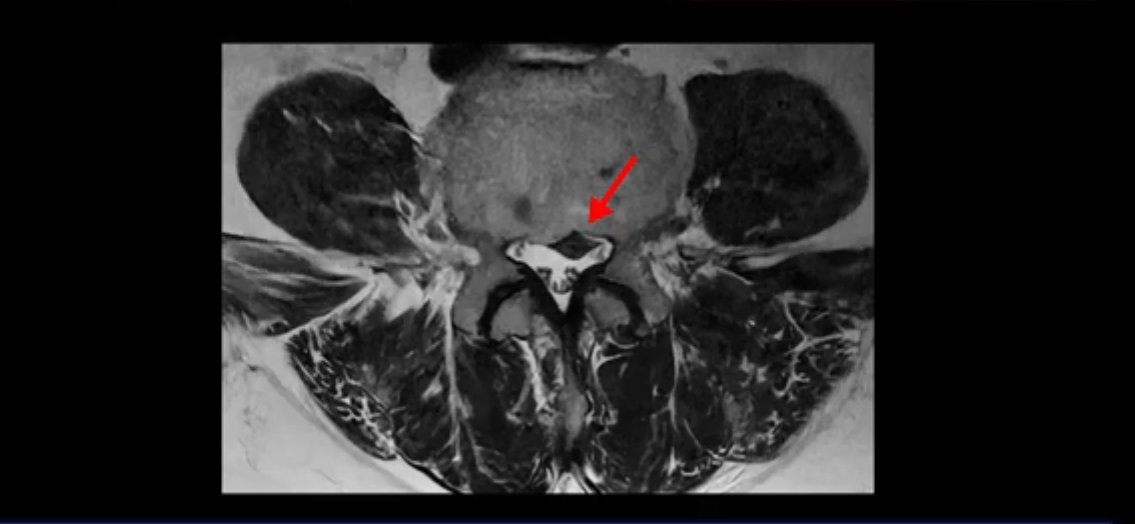

이분 MRI를 잠깐 보실까요? 보시면 두 마디가 특히 안 좋은데 3번 4번 디스크가 터져서 흘러 내려 있습니다.

보시다시피 흘러 내려온 디스크 수핵이 신경 공간의 왼쪽으로 보입니다.

그런데 이분은 4번 5번에도 디스크 파열이 있습니다.

가운데로 심하게 밀려 나와 있는데요.

또 4번 5번에는 협착으로 척추관이 많이 좁아져 있습니다.

또 왼쪽 신경 가지들이 빠져 나가는 신경구멍들이 여러 마디가 좁아져 있습니다.

이런 이유들 때문에 왼쪽 엉덩이부터 종아리, 발가락까지 저리고 아픈 겁니다. 그래서 서둘러 병원에 가셨는데요. 그래서 서둘러 병원에 가셨는데요. 여러분이 꼭 아셔야 할 게 이렇게 다리가 심하게 저리고 아프면 X-ray만 찍을 게 아니고 MRI를 찍어 보시는 게 맞습니다. X-ray로는 디스크가 터졌는지 신경구멍이 좁아진 협착이 있는지를 정확히 할 수가 없습니다. 그래서 이분은 당장 아픈데 해결이 안 되니까 제주도에서 유명하다는 한의원으로 갔습니다.